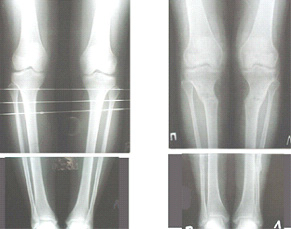

Судя по снимку у девушки имеется внутренняя установка надколенников...

Как у нее с торсионным статусом? Бедро? Голень? КТ? Торсиометры? А то, куда будут

смотреть надколенники после вашей коррекции - тоже существенный

косметический момент. Или не так?

AVM> Судя по снимку у девушки имеется внутренняя установка надколенников...

AVM> Как у нее с торсионным статусом? Бедро? Голень? КТ? Торсиометры?

Похоже, немного есть. Думаю пренебречь.

Картинки - в приложении.Будут вопросы - готов ответить.

Ещё картинка - схема. Хотя у Соломина всё написано.

Вот ещё картинки, которые отправлял в Ортопод. Коррекция кривизны и удлинение на 3 см.